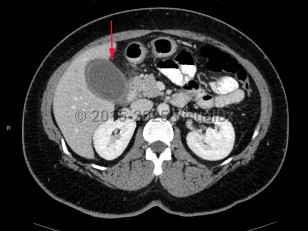

Imaging Studies image of Acute cholecystitis - imageId=7878656. Click to open in gallery.  caption: '<span>CT scan of the abdomen demonstrating distended gallbladder with wall thickening and inflammatory changes in the surrounding fat.</span>'

CT scan of the abdomen demonstrating distended gallbladder with wall thickening and inflammatory changes in the surrounding fat.